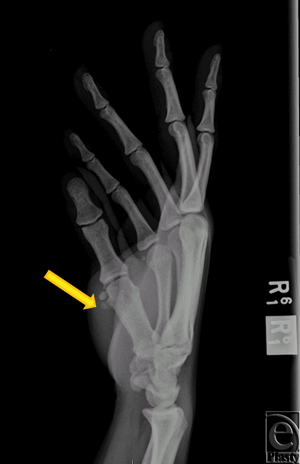

A 31-year-old right hand dominant, African American female presented to the University of Chicago Emergency Department with swelling and progressive pain of her right thumb (first digit) that worsened with activity. She first encountered pain in her previously healthy thumb 2 weeks prior to presentation. She denied trauma and surgery to the affected digit. On physical examination, the digit was erythematous and moderately tender to palpation. Motor function was grossly intact but range of motion (ROM) at the metacarpophalangeal (MP) and interphalangeal joints was reduced because of pain. No neurovascular deficits were noted. There were no palpable masses. The patient was afebrile and a complete blood count and basic metabolic panel were within normal limits. X-rays of the digit revealed radio-opaque masses around the volar aspect of MP joint consistent with synovial chondromatosis without evidence of acute fracture (Fig 1). The digit was managed conservatively and placed in a spica splint. The patient was admitted for empiric antibiotic therapy for suspected cellulitis or abscess in the setting of underlying synovial chondromatosis.

| Figure 1. X-ray. Two 4-mm, radio-opaque masses (arrow) can be visualized alongside the volar and radial aspect of the head of the right first metacarpal bone. No acute fracture is noted. |